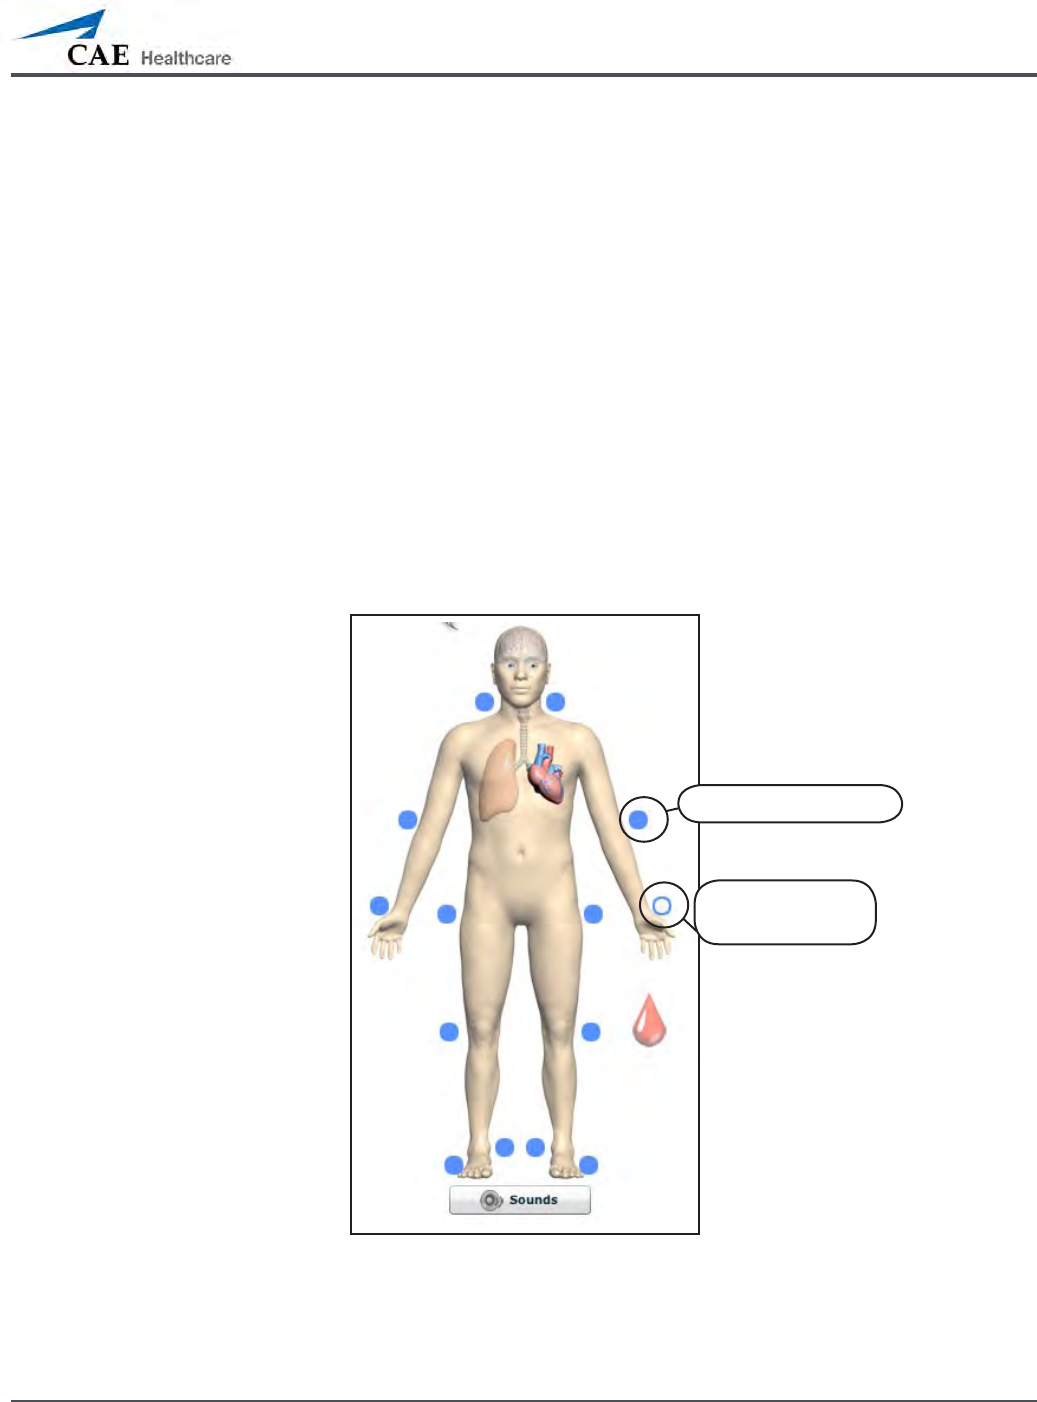

Pulses: METIman Prehospital – Active and Inactive

Activated pulse

Deactivated

pulse

Pulses: METIman Nursing – Active and Inactive

Activated pulse

Deactivated

pulse